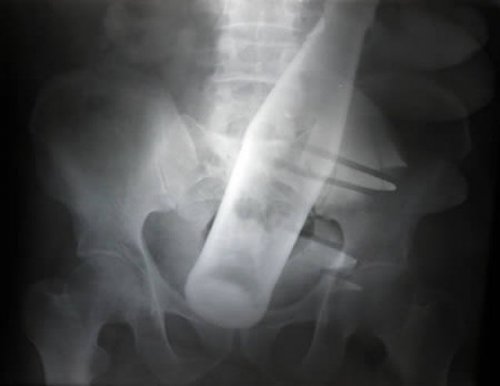

Не забываем и о классических снимках: кружка пива в заднем проходе!

Мужчина из Китая жаловался на боли в желудке. Мужчине пришлось обратиться к врачам после того, как он не смог извлечь бутылки при помощи закрученного куска проволоки. Когда медицинские работники спрашивали его о боли, он утверждал, что не понимает, из-за чего он испытывает дискомфорт. Однако память ему вдруг вернулась, когда врачи показали рентгеновские снимки бутылки и проволоки внутри него. Он подтвердил, что вставил бутылку дома после чего, она застряла, и сказал, что при помощи стальной проволоки попытался вытащить бутылку в приступе паники.![]()